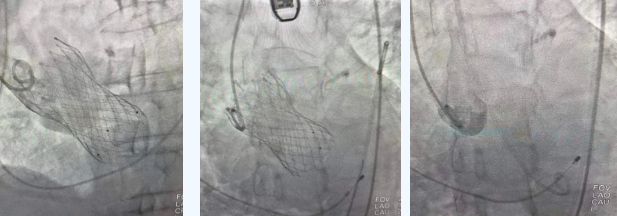

在麻醉手術中心的配合下,曾廣偉主任用導管經(jīng)股動脈鞘進入主動脈瓣目標位置,經(jīng)豬尾導管造影可見主動脈瓣大量返流,因左室流出道較寬,大于瓣膜落腳點直徑,瓣膜釋放位置選擇及釋放難度極大。更為關鍵的是,患者常規(guī)四個錨定點只有一個可以用,定位要極其精準才能保證瓣膜釋放后牢靠,同時不能有大的殘余瘺!稍有移位可能就需要再次植入瓣中瓣或者開刀!

術中,曾廣偉主任團隊高效配合,完成了特定時間點起搏心臟、臨時短時間關閉呼吸機、降低主動脈瓣阻力、快速釋放瓣膜等一系列高難度操作,有效保證瓣膜精準釋放。瓣膜釋放經(jīng)TEE確認,主動脈瓣膜釋放位置佳,經(jīng)豬尾導管造影,主動脈瓣返流即刻消失,且無瓣周瘺。